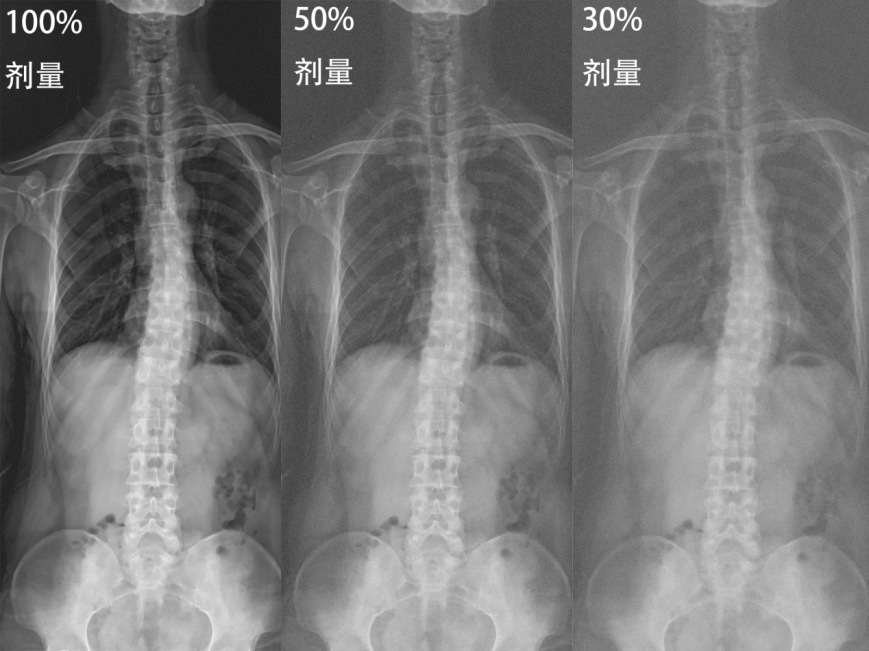

很多家长一提到“拍X线”就会担心辐射问题,这种担心非常理解。以前拍一次脊柱全长的X线,辐射剂量确实不低。更重要的是,孩子们正处于生长发育期,可能需要每2个月至半年就复查一次,长期累积的辐射量让很多家长忧心。但现在有好消息告诉您!现代医学影像技术已经取得了巨大进步。通过先进的数字化设备和智能成像技术,拍摄脊柱X线的辐射剂量已经可以降到原来的三分之一甚至十分之一。一次拍片的辐射量很小,大约相当于我们在自然环境生活中7天所接受的量,风险极低。与其担心这点微乎其微的辐射,不如警惕延误复查可能带来的更大风险。及时检查,才能把握最佳时机,这才是真正明智和安心的选择。

图3 版权图片 不授权转载